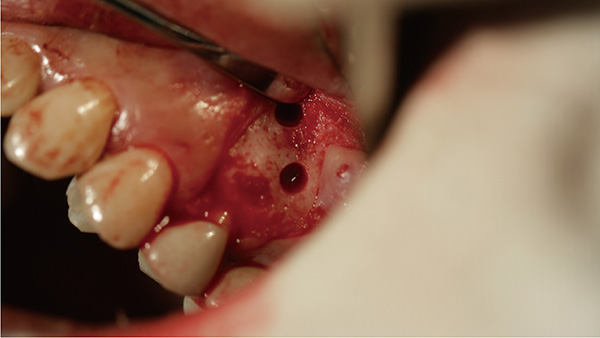

覆蓋所有牙位、即刻種植、即拔即種、全口無牙頜種植